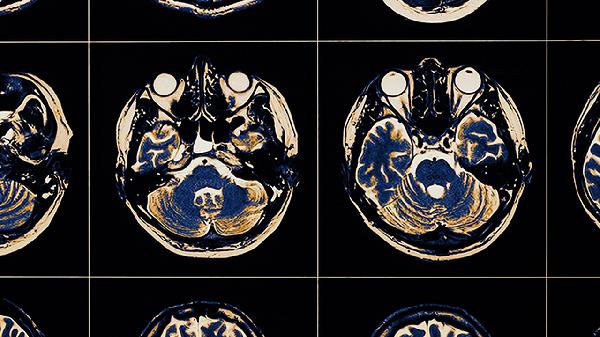

患兒恢復期需保證每日優(yōu)質蛋白攝入,如魚肉、蛋類等富含卵磷脂的食物。避免劇烈運動但需維持每日30分鐘步行訓練。居家環(huán)境應移除尖銳物品,床邊加裝護欄。定期復查腦電圖和頭顱MRI評估恢復情況,若出現(xiàn)抽搐或意識模糊需立即返院。保持規(guī)律作息與愉悅情緒對神經功能修復至關重要。